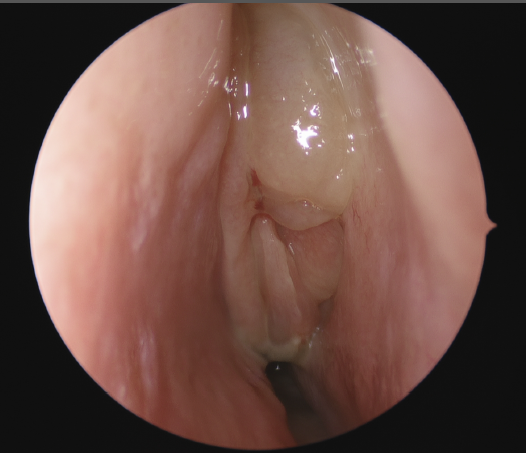

Chronic rhinosinusitis afflicts over 30 million patients in the USA annually, or roughly 12.5% of the population. It has tremendous impacts on the economy and on a patient’s quality of life. It is defined as symptoms of sinonasal inflammation lasting at least twelve consecutive weeks with corresponding objective physical findings. Symptoms may include nasal obstruction, congestion, nasal drainage, post-nasal drip, facial pressure, loss of smell and/or taste, fever, fatigue, and dental pain. To examine for sinonasal inflammation your physician will use a nasal endoscope to evaluate your nasal cavities and paranasal sinuses. You may also undergo computed tomography (CT) or another form of imaging.

Medical management is typically the primary treatment approach for chronic rhinosinusitis and may include saline nasal irrigations, intranasal corticosteroid sprays, antibiotics, systemic corticosteroids, and allergy pills. If medical treatment fails, endoscopic sinus surgery is the next step in management. The goals of surgery are to reestablish drainage pathways for the paranasal sinuses with large openings that allow the delivery of irrigations and topical medications. The routine postoperative course consists of regular nasal endoscopies to debride the postsurgical sinus cavities and to ensure proper healing.